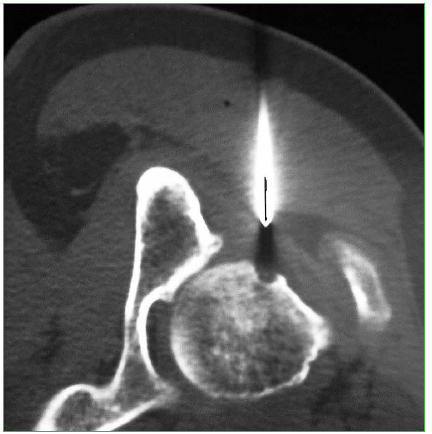

Figura 8.

Resonancia magnética de cadera derecha, corte coronal en secuencias potenciadas en STIR (A) y T1 (B). Se observa edema óseo (aumento de la señal) que afecta al cuello femoral, con un pequeño trazo de fractura trabecular (flecha) asociado a derrame articular en un paciente maratonista.